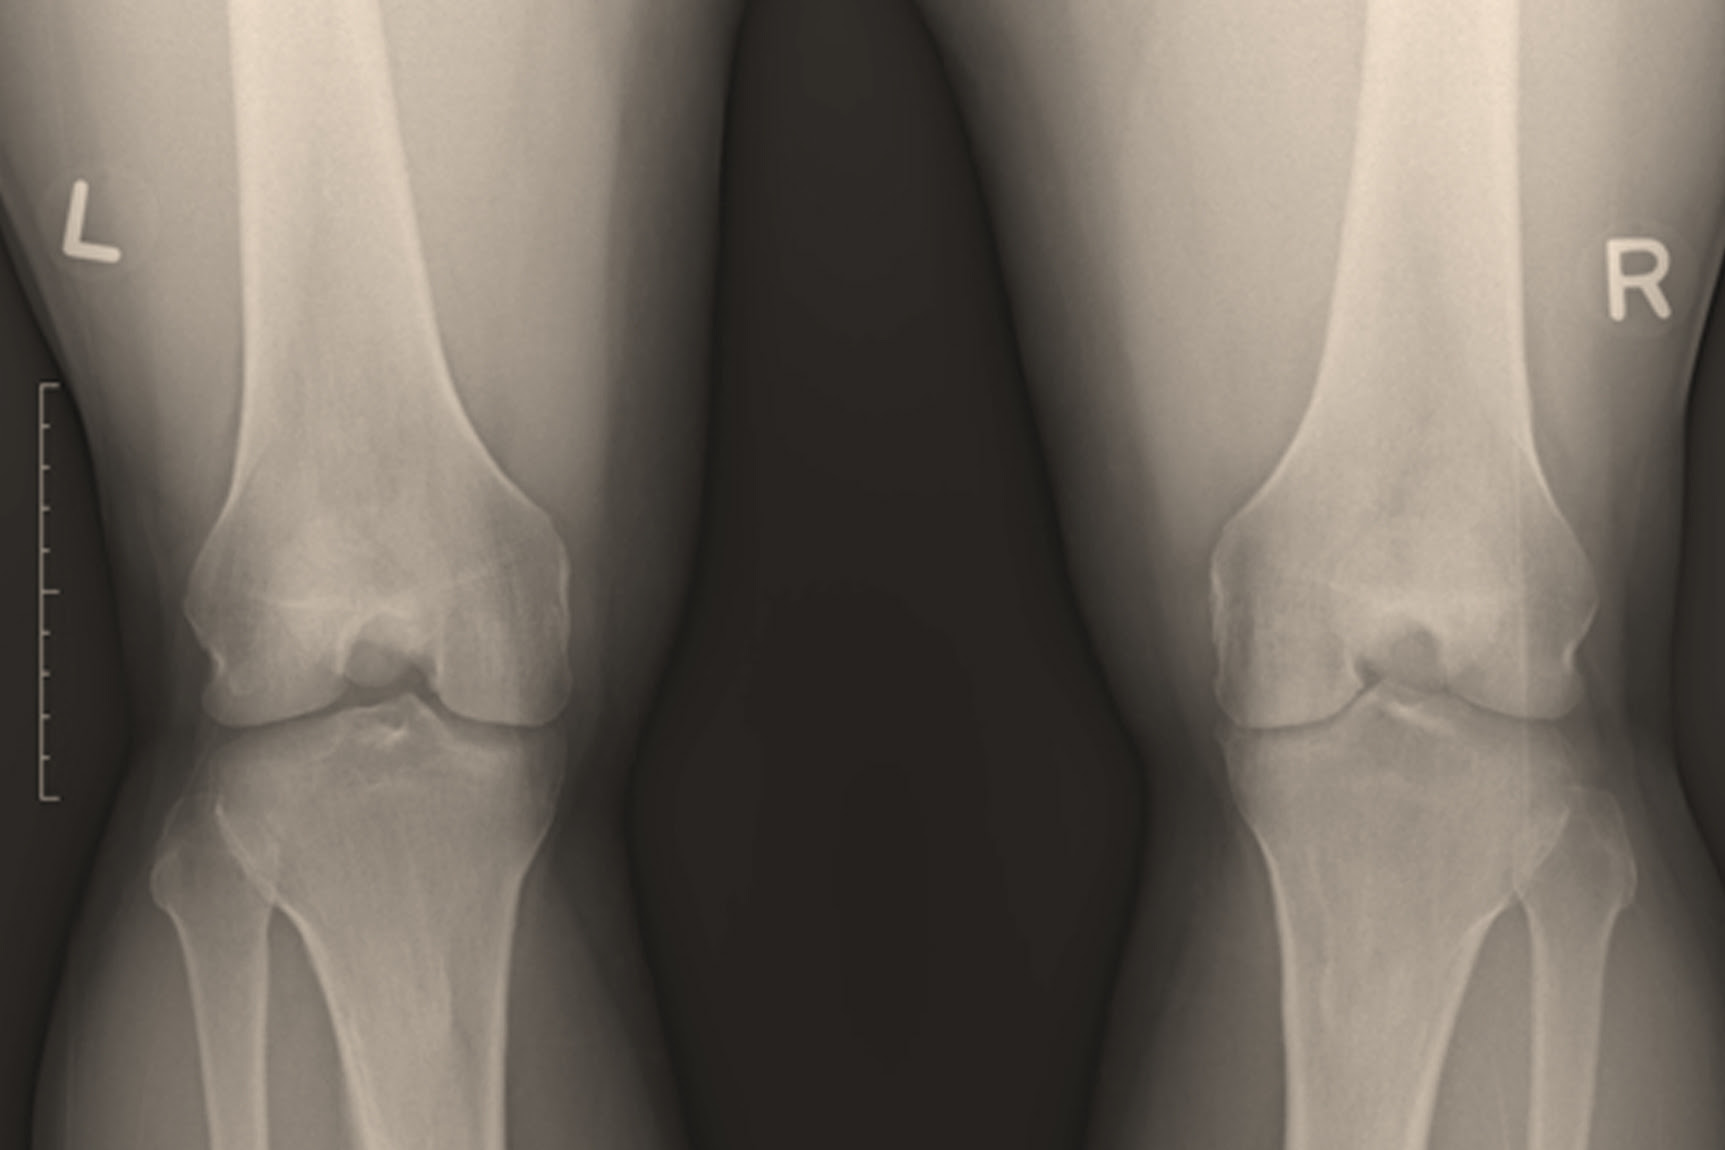

If you notice a bone deformity after an injury, he recommends seeking the assistance of an orthopedic doctor immediately. The doctor will likely take x-rays as well as perform a visual diagnosis to determine if you need surgery.

He or she will look at both knees and check for tenderness and range of motion and see how stable your knee is. You may also have X-rays or an MRI.

- X-rays to check for injuries to the bones

For knee pain, patients are always referred for x-rays, as this examination helps the doctor more accurately assess the condition of the knee joint. An X-ray taken in a standing position gives an idea of the thickness of the cartilage tissue. Thus, the specialists of our clinic can rule out that the cause of the stitching pain in the knee is arthrosis of the knee joint.Concomitant injuries of sprains, curvatures or dislocations of the knee joint can also be bone injuries. With the help of an X-ray, orthopedic specialists at Gelenk-Clinic will be able to exclude the presence of fractures.